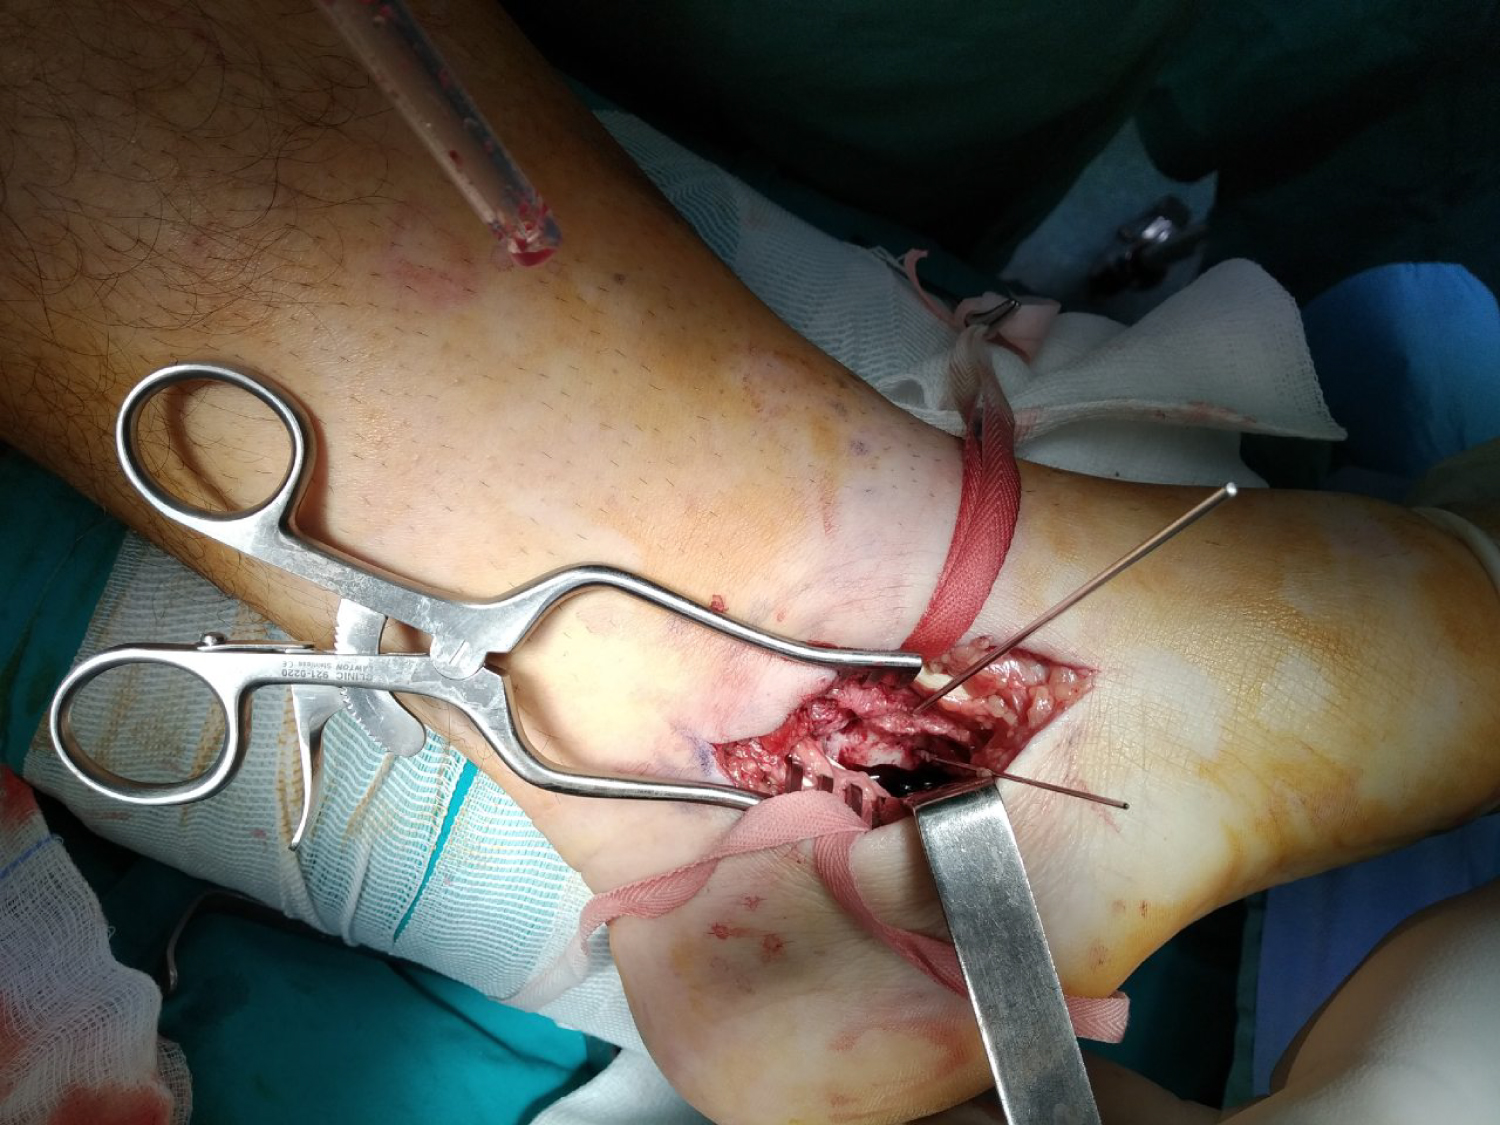

The patient was applied supine on the surgical table and a thigh tourniquet was applied. A medial incision 2 cm distal to the tip of the medial malleolus was performed, extending to the tuberosity of the navicular bone. Tibialis posterior and flexor digitorum longus were identified and protected (Figure 6). The plan between those two tendons was used to approach the sustentaculum (Figure 7). Care was taken not to violate the neurovascular structures, which they normally course posteriorly and inferiorly to the flexor digitorum longus. The fracture of the sustentaculum tali was identified, reduced under direct visualization of the medial calcaneal cortex and stabilized provisionally with Kirschner Wires (KW), under fluoroscopic control (Figure 8). Two spongiosa, partially threaded, cannulated 4.0 mm screws were used to fix the fracture. A buttress plate was also applied for stronger stabilization. An anterolateral ankle incision was performed starting approximately 4 cm above the level of the ankle joint extending distally, just proximally to the base of the 4th metatarsal. As it was decided preoperatively, a distal fibular door osteotomy was performed in order to approach the fracture of the lateral talar body. Anterior inferior tibiofibular ligament (AITFL) and the anterior talofibular ligament (ATFL) were sharply dissected. Distal fibula was transversely osteotomized 2 cm above the ankle joint. The distal part of the osteotomy was externally rotated revealing the area of the fracture. Fracture of the lateral talar body was fixed with two partially threaded cannulated compression headless 3.0 mm screws. Fluoroscopic imaging confirmed the correct reduction of the fracture and position of the screws. Distal fibula was fixed with one third tubular plate. AITFL and ATFL were repaired with a 2/0 absorbable suture. Postoperative radiographs were shown (Figure 9, Figure 10, and Figure 11).

Figure 6: Intraoperative view. Surgical plan between tibialis posterior and flexor digitorum longus tendon. View Figure 6

Figure 7: Intraoperative view. Sustentaculum tali fracture exposure. View Figure 7

Figure 8: Intraoperative view. Fracture reduction and provisional stabilization with KW. View Figure 8